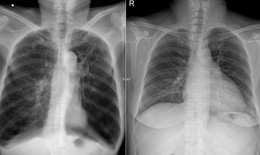

Bệnh trẻ em - 21/10/2025 14:34SKĐS - Viêm phổi là bệnh lý nhiễm trùng phổ biến, gây tổn thương nhu mô phổi và đi kèm các triệu chứng như ho, khó thở, nhịp thở nhanh, đau ngực…Bệnh có tỷ lệ mắc và tử vong cao, đặc biệt ở trẻ dưới 5 tuổi.

Bệnh trẻ em - 06/07/2025 17:24SKĐS - Viêm phổi là một bệnh truyền nhiễm, tấn công trực tiếp vào phổi và gây viêm. Đây là bệnh hô hấp nguy hiểm, đặc biệt là với trẻ sơ sinh. Việc nhận biết sớm và phát hiện mức độ nguy hiểm của bệnh để đưa trẻ đi viện điều trị kịp thời là vô cùng quan trọng.

Bệnh thường gặp - 26/02/2025 06:00SKĐS - Viêm phổi cấp là bệnh lý nhiễm trùng cấp tính ở phổi, bệnh diễn biến nhanh và phức tạp. Vì vậy, khi được chẩn đoán viêm phổi cấp khiến nhiều bệnh nhân lo lắng. Vậy viêm phổi cấp do đâu, nguy hiểm thế nào?